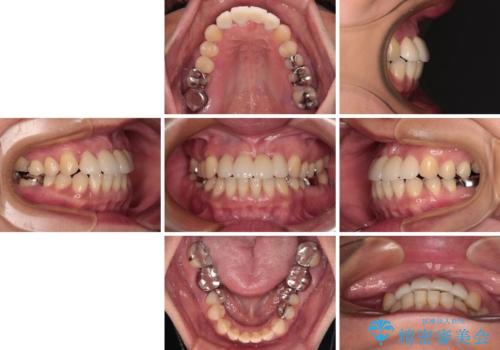

中途半端な矯正治療と前歯の欠損 再矯正とオールセラミッククラウンによる補綴治療

- 矯正治療を行ったものの、隙間やデコボコが多く、欠損している前歯も気になるとのことで来院された患者様です。

当初はセラミック治療だけを希望されていましたが、上下前歯のデコボコが顕著であったため、セラミッククラウンにて治療する前に再度矯正治療を行った方が仕上がりがきれいになると説明し、再矯正を行うこととしました。

矯正治療により前歯横幅のバランスを整えた後に、上顎前歯をオールセラミックブリッジにて補綴治療を行うこととしました。

舌突出癖により、上下前歯が突出して離開してしまったため、舌のトレーニングを徹底的に行いました。